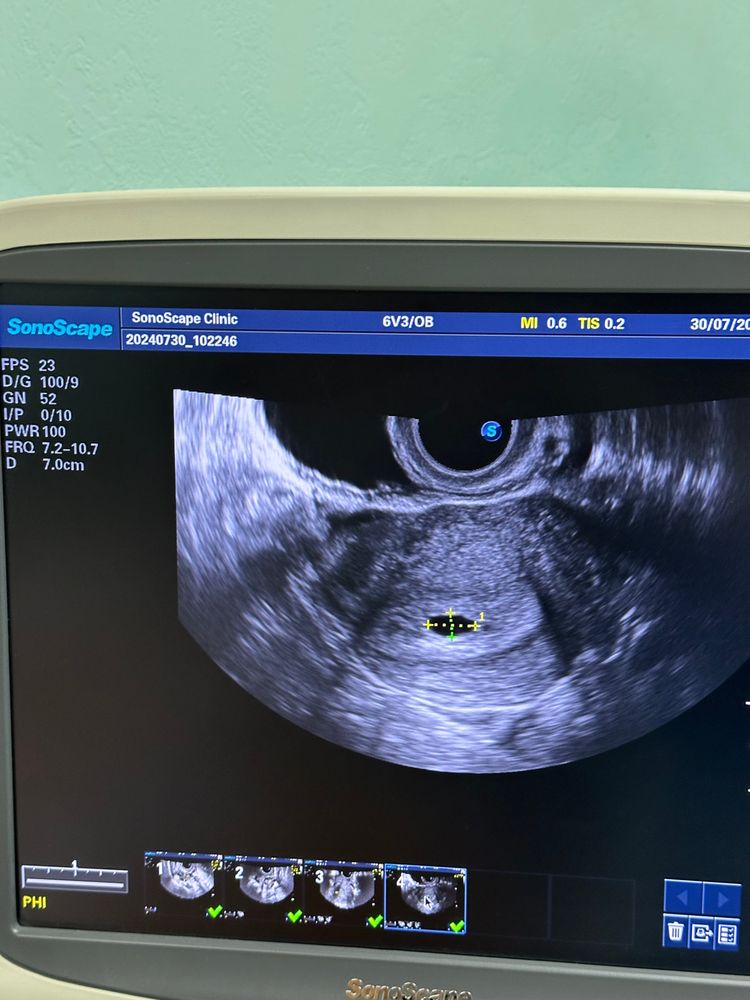

УЗИ 21 дпп

Результаты УЗИДевочки, была сегодня на узи 21 дпп, посмотрели очень быстро, только сам факт наличия пя в матке, а я растерялась, не спросила про жм, теперь переживаю😕 УЗИ в доступности сейчас только такое, за более качественным аппаратом нужно ехать.

Это нормально что пя вытянутое? 10,6 на 5,6.

Мне кажется в правом углу что-то есть или кажется, все фото с замерами. У меня была точно такая же форма на 18дпп, ничего страшного. Про жм тоже сказали что нет, но мне кажется на фото в нижнем углу он был. Рано еще переживать, у вас хгч пониже.

Ирина, слушайте, точно, под цифрой 1 на моих снимках как будто что то есть🙏🏻 фото без замеров нет к сожалению. Спасибо 🙏🏻🙏🏻🙏🏻 А дальше у вас какие результаты узи?